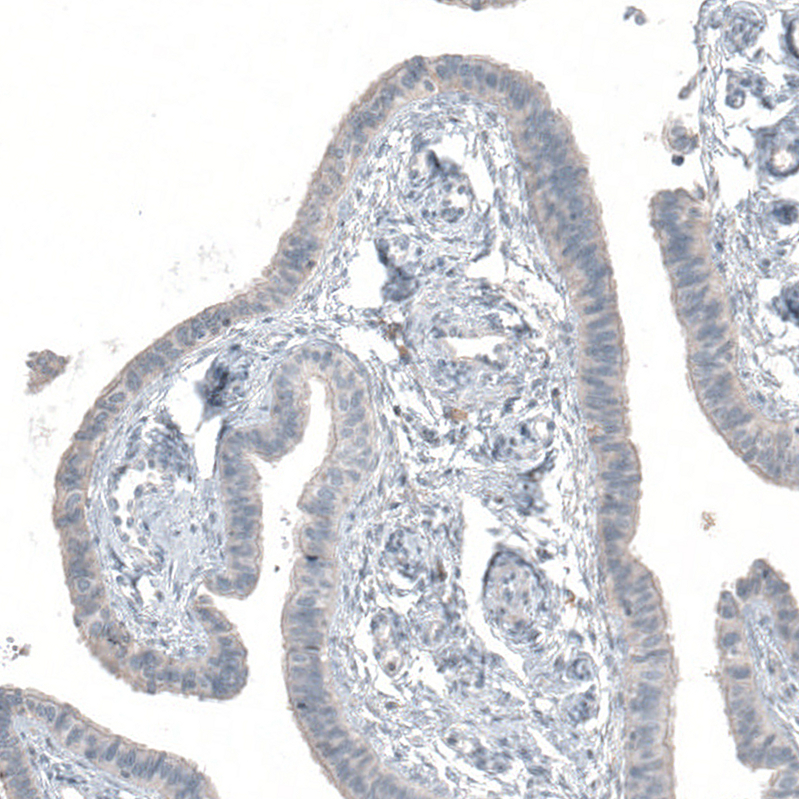

Immunohistochemical staining of human testis shows moderate to strong cytoplasmic positivity in cells in seminiferous ducts.